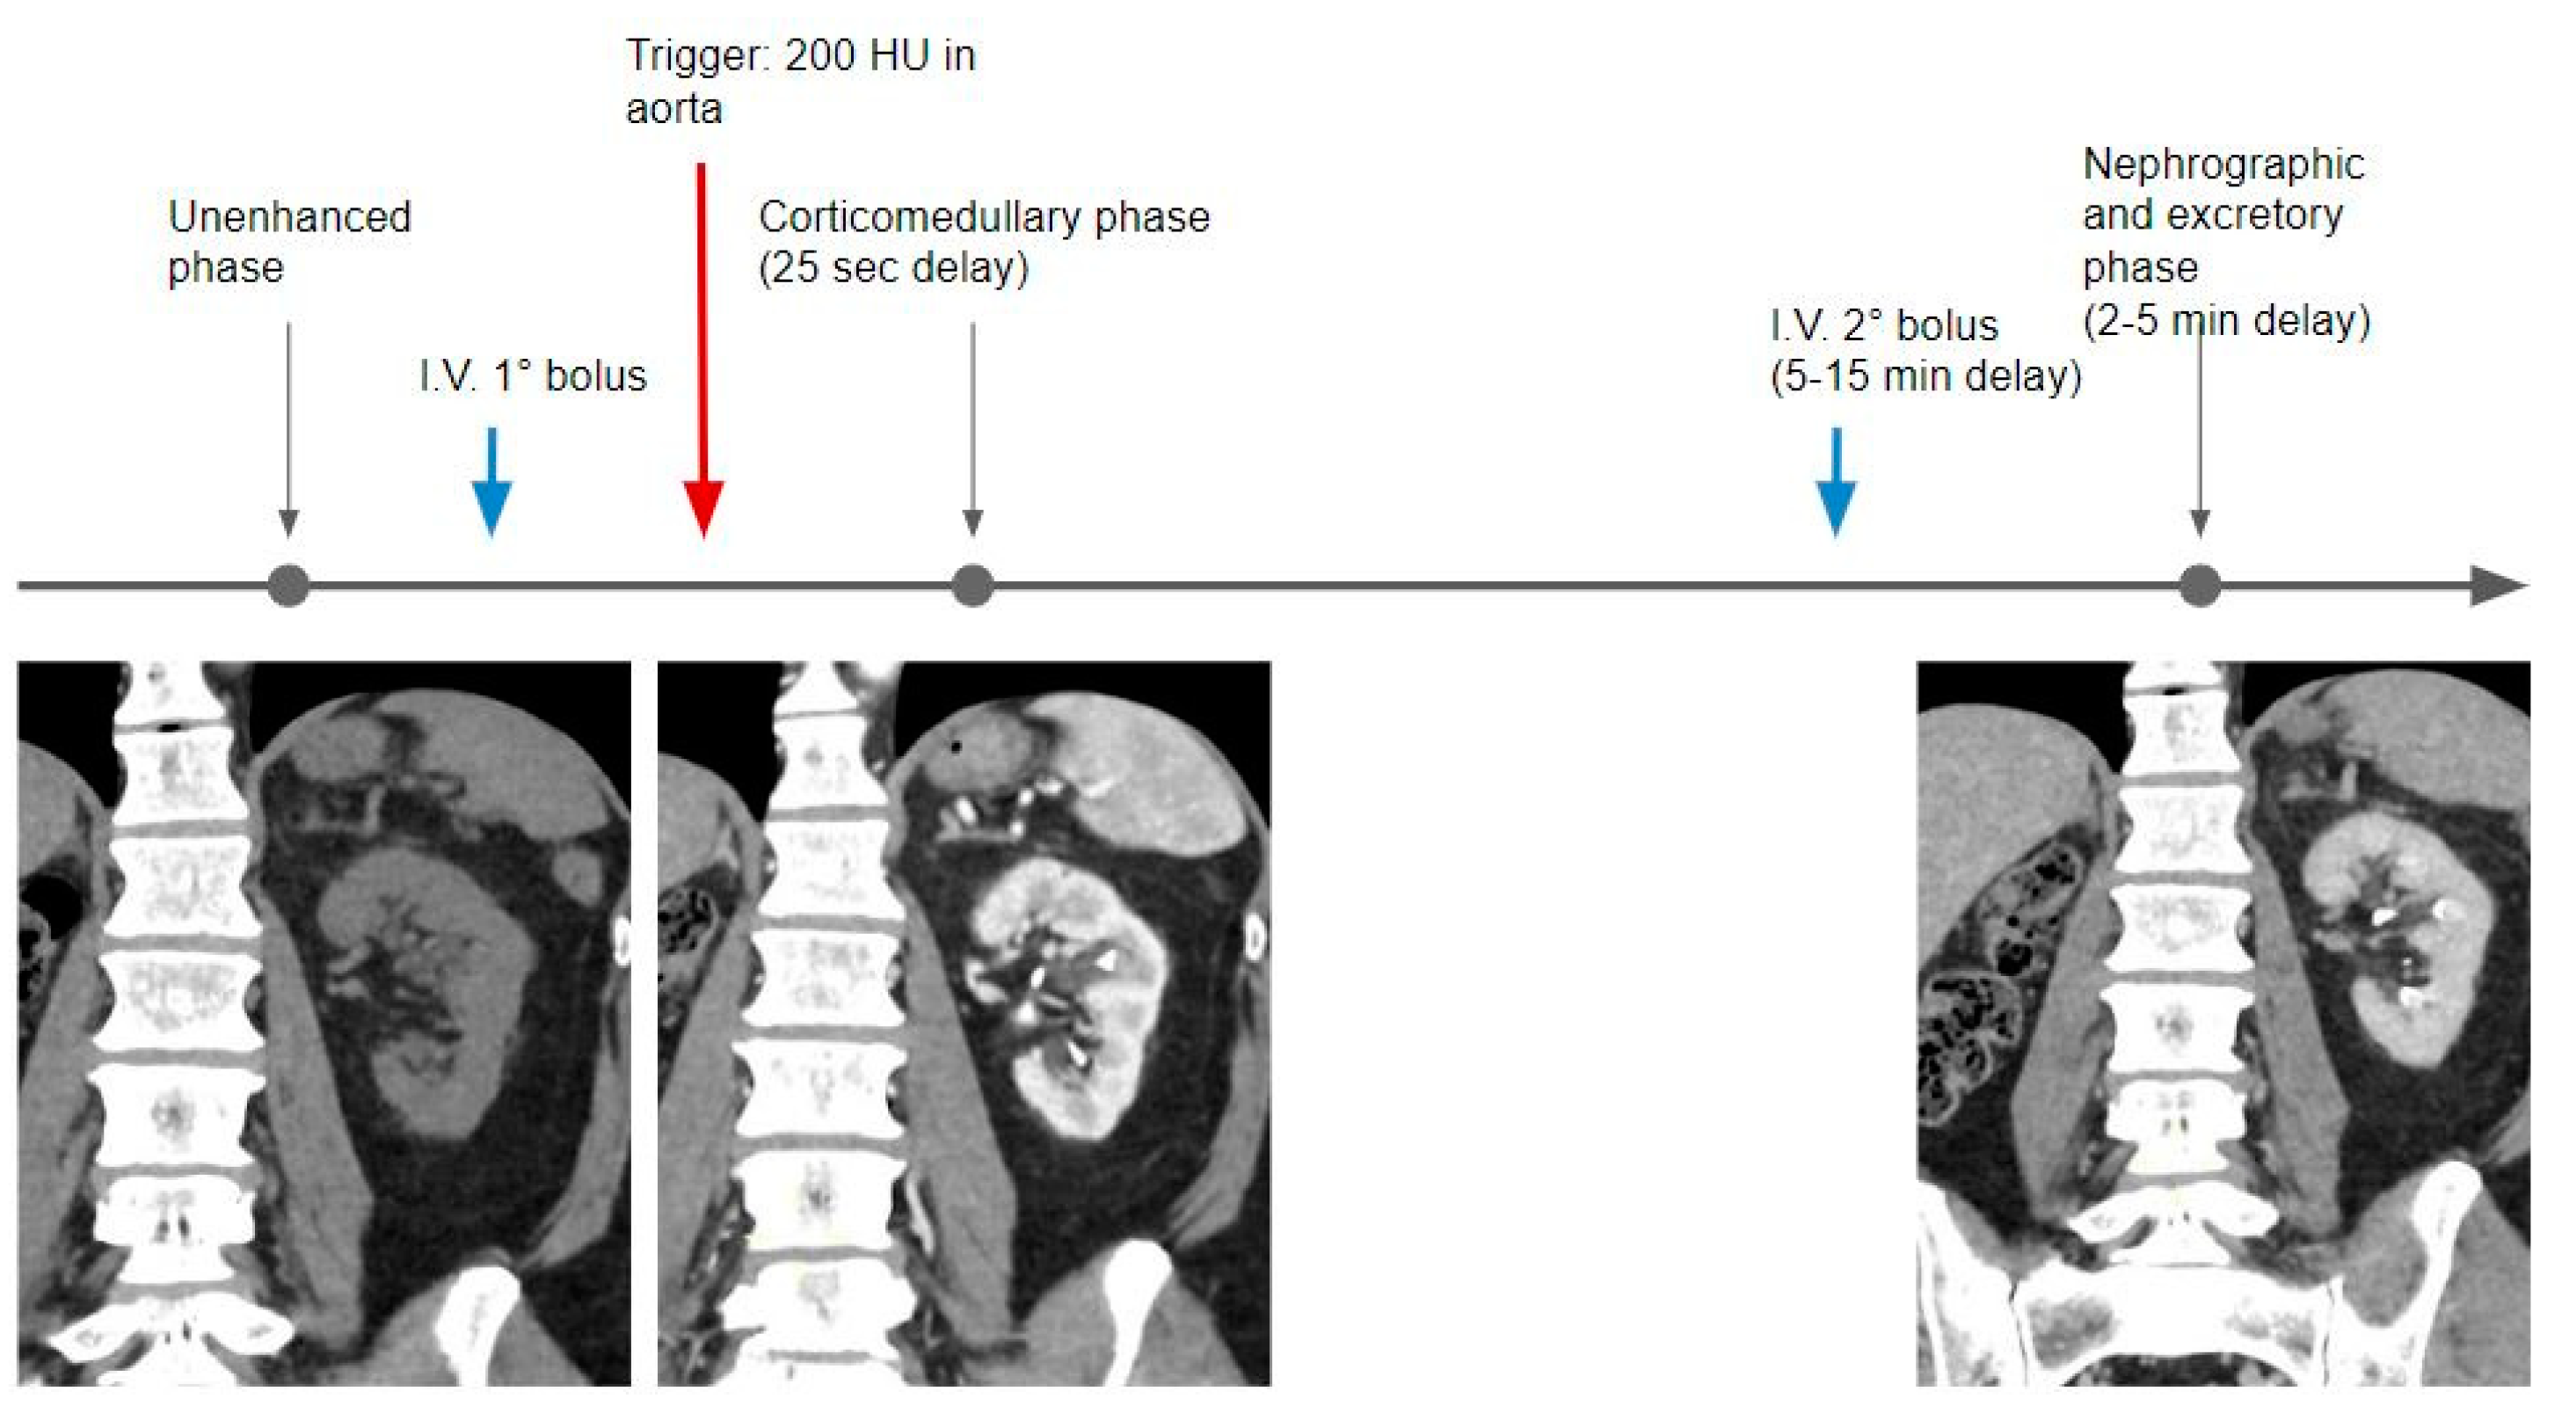

Figure 3.

Graphical representation of the single bolus acquisition technique.

The first acquired phase is the CMP, usually acquired with a bolus tracking technique, placing a region of interest in the abdominal aorta, with a threshold of 200 HU, with an estimated acquisition delay set at 25 s. In this phase, the kidney contrast enhancement is related to the arterial inflow. The nephrographic phase is then acquired at a delay of about 40 s when the renal parenchyma is almost homogeneous in density.

In the excretory phase, the renal parenchyma is homogeneous but characterized by a markedly reduced density in comparison with the previous phases, with the calyces and pelvis filled with iodinated urine.

In the split bolus technique, after the unenhanced phase, the first portion of the whole contrast medium dose is administered (usually one-third or half); then, using the bolus tracking technique and a delay of 25 s, the corticomedullary phase is acquired. A second bolus of contrast medium is injected at a variable timing (5–10 min of delay), followed by a third CT acquisition, where the kidneys are in the nephrographic phase and the calyces and pelvis are filled with iodinated urine.

In this protocol, the contrast bolus is administered in two separate injections. After the unenhanced phase, the first part (usually one-third or half) of the contrast is injected and the optional CMP is obtained, then the second part of the contrast (usually a dose larger than or equal to the first one), is injected about 5–10 min later, and combined nephrographic–excretory phase images are acquired at 2–5 min when the kidneys show enhancement of the renal parenchyma and opacification of the collecting systems occurs [7] (Table 2).